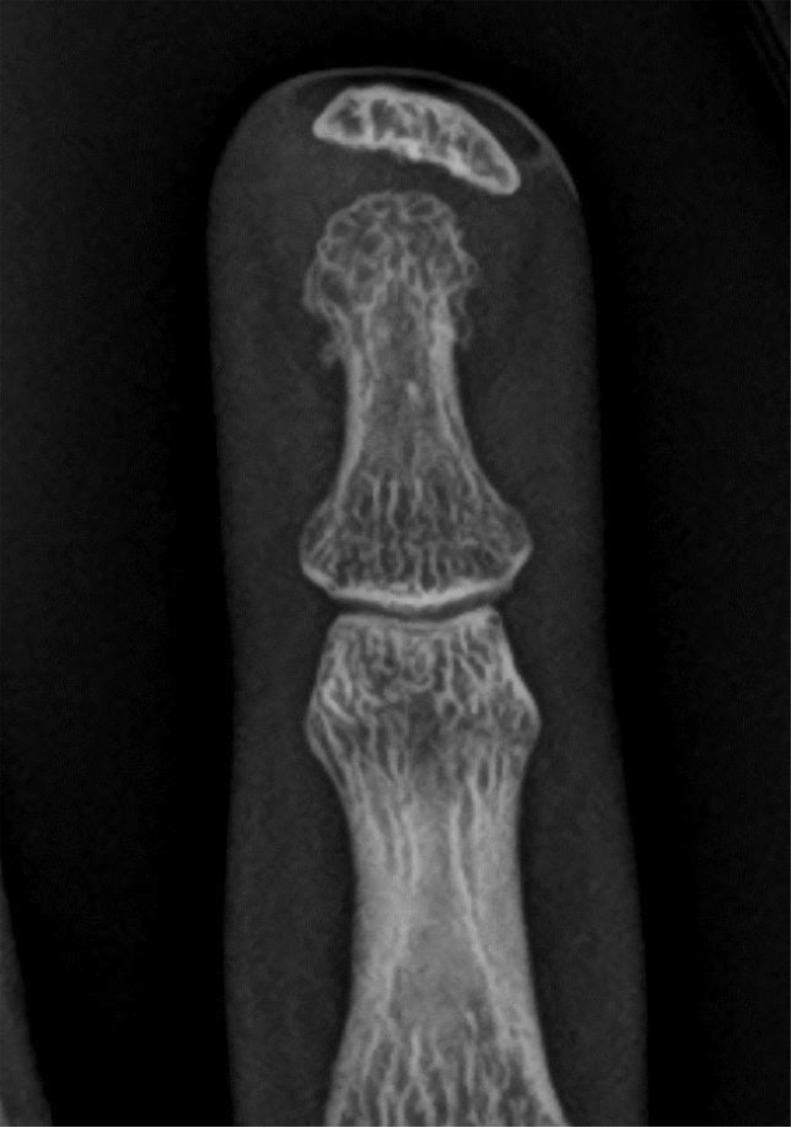

Eight days later, the patient returned to the emergency department with an infected ring finger, in excruciating pain. To monitor her blood sugar, the patient reported performing daily finger pricks using her index, middle, and ring fingers. On physical examination, the tip of her ring finger was swollen, black, and oozing pus. She was admitted for IV antibiotic and pain management, pending surgical debridement. During this admission, a radiographic series of the ring finger was obtained to rule out osteomyelitis. There was no radiographic evidence of osteomyelitis. However, in the soft tissue of the fingertip at the site of the open wound, there is a 1.0 × 0.3 × 0.8 cm well-circumscribed dense structure, separate from the adjacent intact distal phalanx. On radiographs, it has the density and appearance of bone (Figs. 1 and 2). The radiologist described the finding as a bony structure, with cortical bone and bone marrow matrix, interpreting it as a heterotopic ossification in a very unusual location.

Fig. 1.

Anteroposterior radiograph of the ring finger exhibits a well-demarcated dense structure at the fingertip, separate from the distal phalanx. It has the appearance of bone, with bone cortex and bone marrow matrix. There is no evidence of bony destruction to suggest osteomyelitis.